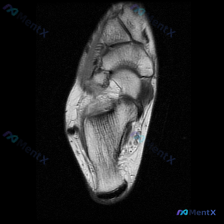

分享一例足部MRI T2加权矢状位读片,整理了完整思路和大家讨论。 病例基本影像信息 本次分析的是足部MRI T2加权矢状位图像,原始问题是观察是否存在软骨异常,我们先把所有影像发现整理清楚: 1. 骨骼结构:跟骨、距骨、舟骨、楔骨及跖骨结构完整,骨皮质连续,未见骨折线;骨髓信号整体正常,未见弥漫性...